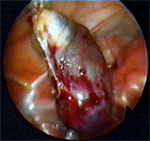

След създаване на пневмоперитонеум до 12 mmHg се въвеждат 3 троакара – един умбиликален от 10 mm за оптиката и два супрапубични от 5 mm за инструменти. След освобождаване на маточните тръби от срастванията със съседните органи чрез биполярна коагулация на мезосалпинкса и последващото му прерязване се отстранява тръбата в максимална близост до матката. Следва екстирпация на хидросалпинкса през 10 mm троакар .

Коагулация на мезосалпинкса и последващата му резекция